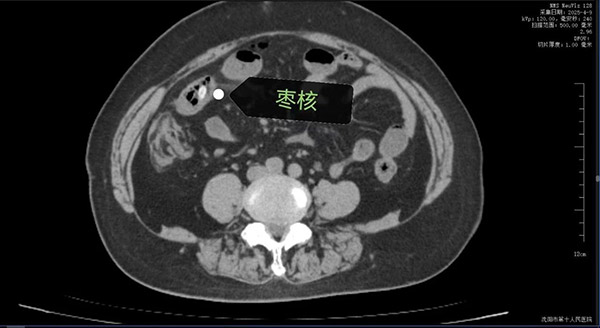

63岁的康阿姨因突发"刀绞般"的剧烈腹痛被深夜紧急送往沈阳市第十人民医院(沈阳市胸科医院)。短短数小时内,她已出现高热、腹肌强直等弥漫性腹膜炎症状,CT检查显示其腹腔内游离气体,高度怀疑消化道穿孔。追问病史时家属猛然回忆:今天上午康阿姨吃粽子时误将两颗枣核吞下!沈阳市第十人民医院(沈阳市胸科医院)普外科任庆华主任团队火速会诊,判断枣核尖端已刺穿小肠,必须立即手术。

凌晨的手术室里,任庆华主任与刘晓斌副主任医师打开腹腔时,眼前的场景令人心惊:大量浑浊脓液涌出,两枚长达3cm的尖锐枣核分别嵌顿在幽门处与回肠段,其中远端小肠已形成两处直径0.8cm的穿孔,两处约10cm及5厘米肠管因缺血呈黑紫色。医疗团队当机立断,行"胃切开异物取出术"完整取出胃内枣核后,针对坏死肠段实施精准的"小肠多节段部分切除术",同时分解患者既往腹部手术形成的致密粘连。凭借丰富的临床经验,团队在确保彻底清除感染灶的前提下,最大限度保留了健康肠管。